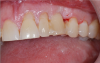

The first case involved a 45-year-old man presenting with the complaint that his dentist told him they could not put a tooth on his implant. He was also unhappy with an implant that was placed too supragingivally. The healing cap was in contact with the distal tooth. The implant was not restorable in the position it was placed (Figure 3). If the patient were willing to undergo orthodontics, there may have been a chance to place a tooth on the implant. In the end, though, no matter what the clinician was able to place or how the adjacent teeth were modified, the result would not be optimal.

Fig 3. Non-restorable implant that would have benefited from collaboration earlier.

Figure 3